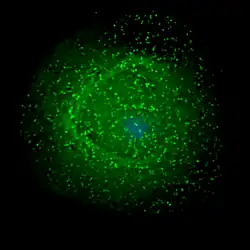

| Scanning electron micrograph of HIV-1 (in green) budding from cultured lymphocyte. Multiple round bumps on cell surface represent sites of assembly and budding of virions. | |